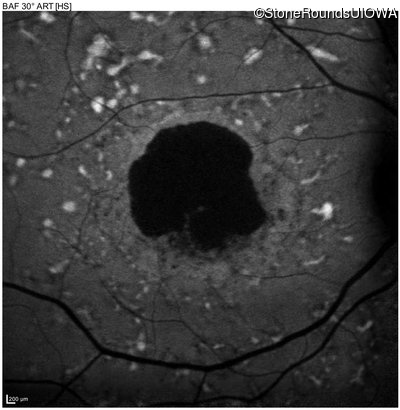

AR Stargardt Disease (IIA)

Age at visit: 59 years

Diagnosis & molecular findings

AR Stargardt Disease ABCA4 Glu471Lys GAA>AAA / Glu2131Lys GAA>AAA Asp2181 del36gaCCTGAACCCTGTGGAGCAGTTCTTCCAGGGGAACTT AR